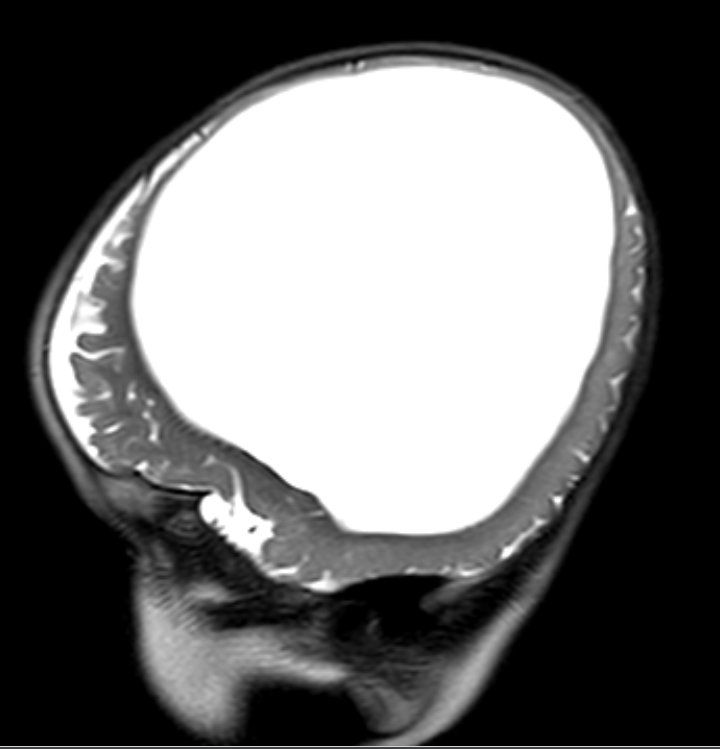

As Seth’s neighbor explained to us, “Seth is missing 95% of his brain or more. By the miracle of god and the child’s will to prove everyone wrong he celebrated his 4th birthday this year (2017). Unfortunately with the child missing so much of his brain he cannot walk, see, talk, and has very, very limited muscle control, on top of all these problems he also has seizures through out the day and night.”

After meeting with lots of specialists and doing research, the plan was for Seth to have surgery after birth to the fluid around the brain allowing it to expand. The hospital in Boston has the most experienced neurosurgeon and I flew there at 34 weeks. Seth was born at 39 weeks. I named him Seth after Adam and Eve’s 3rd child. A few days after birth, Seth had surgery to remove the fluid. There was a lot of waiting and a lot of tests after the surgery to figure out why his head was still full of fluid. Finally, at a meeting with 13 doctors they showed me Seth’s MRI, which showed he was missing his brain and fluid was in its place. This is called hydransephaly. I was told it was extremely rare and that he would not survive. I had him baptized and we spent two weeks at the hospital in Boston. I decided to fly us back home so my family could meet him and help plan his funeral.